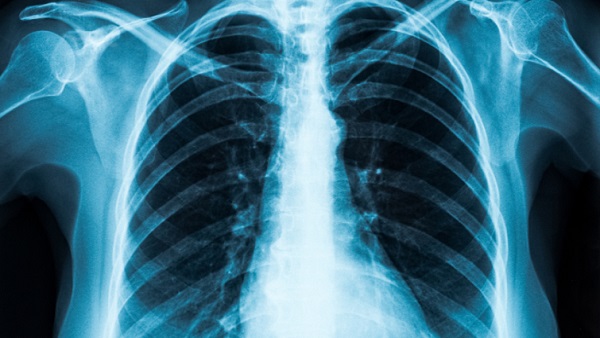

नई दिल्ली, 20 जनवरी: अब वैज्ञानिकों ने कोरोना जांच के लिए एक नया तरीका खोज लिया है, अब एक्स-रे के जरिए भी कोविड-19 की जांच की जा सकेगी। स्कॉटलैंड में वैज्ञानिकों के एक ग्रुप ने एक्स-रे का उपयोग करने वाले व्यक्ति में कोरोना वायरस रोग (कोविड -19) संक्रमण की उपस्थिति का पता लगाने का एक तरीका खोजा है। ये जांच किसी भी व्यक्ति के अंदर कोरोना की उपस्थिति की भविष्यवाणी करने के लिए कृत्रिम बुद्धि (एआई) का उपयोग करता है। ये परीक्षण वेस्ट स्कॉटलैंड विश्वविद्यालय (यूडब्ल्यूएस) के वैज्ञानिकों ने विकसित किया है। उनका दावा है कि ये 98 प्रतिशत प्रभावी है।

यूडब्ल्यूएस के शोधकर्ताओं के मुताबिक नई तकनीक स्कैन की तुलना लगभग 3,000 छवियों के डेटाबेस से करने के लिए एक्स-रे तकनीक का उपयोग करती है, जो कोवि -19 के रोगियों, स्वस्थ व्यक्तियों और वायरल निमोनिया से संबंधित हैं। ये एक एआई प्रक्रिया है, जिसे डीप कन्वेन्शनल न्यूरल नेटवर्क के रूप में जाना जाता है। इस प्रक्रिया में इमेजरी का विश्लेषण करने और निदान करने के लिए एक एल्गोरिथ्म का उपयोग करता है। यूडब्ल्यूएस के वैज्ञानिकों का कहना है कि ये एक व्यापक परीक्षण चरण के दौरान तकनीक 98 प्रतिशत से अधिक सटीक साबित हुई।